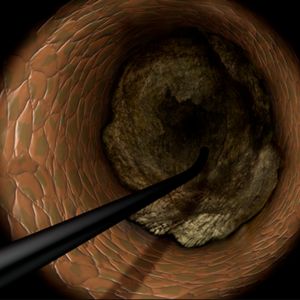

From the era of Plain Old Balloon Angioplasty (POBA) to bare-metal stents (BMS) and subsequently drug-eluting stents (DES), PCI has evolved to become the primary treatment modality for increasingly complex lesions. Among these, chronic total occlusions (CTOs) were considered the "last frontier" of PCI, prompting the development of techniques to guide wires through completely occluded lesions.

In Japan, PCI evolved under the unique circumstances of a universal healthcare system, where fewer restrictions on time and cost allowed for more flexible approaches compared to Western countries. From the late 1990s to the early 2000s, innovative techniques such as the parallel wire technique and IVUS-guided wiring emerged in Japan. However, despite the implementation of these methods, initial technical success rates for CTO-PCI remained around 80%.

In the mid-to-late 2000s, the retrograde approach was introduced, leveraging collateral channels for wire crossing, significantly improving the success rates of CTO-PCI. This technique gained widespread attention due to the expertise of Japanese operators, elevating the global recognition of Japan's contributions. However, the use of delicate collateral channels posed challenges, particularly for less experienced interventional cardiologists, leading to complications such as perforations. Consequently, enthusiasm for CTO-PCI waned in Western countries, where its perceived lack of reproducibility kept it relegated to the realm of mastery-level procedures.

A new wave of technological innovation emerged in the late 2010s with the introduction of the 3D wiring technique. Developed by Dr. Atsunori Okamura of Sakurabashi Watanabe Hospital, this method enabled three-dimensional visualization of wires within occluded lesions, allowing precise manipulation by observing the movement of the wire tip in three dimensions. This rational approach transitioned CTO-PCI wiring from a skill dependent on tactile sensation to one guided by scientific observation.

The 3D wiring technique was further refined by expert operators across Japan, eventually establishing Tip Detection Antegrade Dissection Re-entry (TD-ADR) as a new standard in CTO-PCI. TD-ADR reignited global interest in CTO-PCI by providing a more systematic and reproducible methodology. More recently, HydroDynamic Contrast Recanalization (HDR) has emerged as a technique for performing antegrade CTO-PCI, leveraging the synergistic use of contrast microinjections and polymer-jacketed wires to further expand the technical options available for CTO-PCI.

Compared to conventional approaches to CTO-PCI, the emergence of TD-ADR and HDR has significantly reduced costs, procedure times, and complication risks. These advancements inspire confidence that CTO-PCI, often referred to as the "last frontier" of PCI, could become a fundamental treatment for totally occluded lesions.